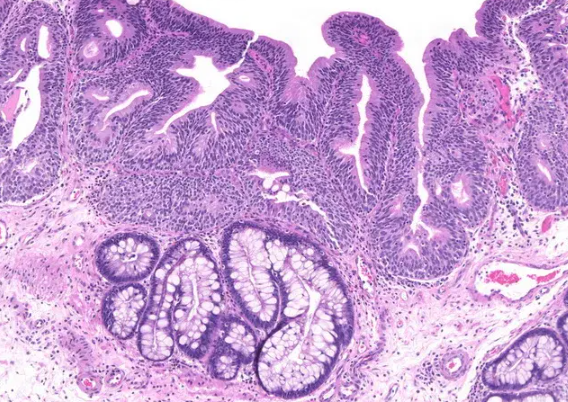

장상피화생은 위 점막이 장 점막처럼 바뀌는 현상입니다. 위 점막은 본래 산성 환경에서 잘 버틸 수 있도록 구성되어 있지만, 오랜 기간 위염이나 헬리코박터균 등에 의해 자극을 받을 경우 장 세포처럼 변형되기도 합니다. 이는 위의 방어기능이 약해졌다는 신호로 볼 수 있지요.

결론부터 이야기하면, 장상피화생이 곧바로 암이 되는 것은 아니며, 그 과정은 매우 느리고 개별적인 요소에 따라 달라집니다. 문헌이나 연구자료를 보면 일부 환자에서 10년 이상 걸리기도 하며, 암으로 진행되지 않는 경우도 많습니다.

하지만 중요한 건 그 '가능성'이 존재한다는 것입니다. 저도 검색을 통해 알게 되었는데, 특히 장상피화생이 '광범위하거나', '불완전형'일 경우 위험도가 올라간다는 연구 결과들이 있었습니다. 물론 이것이 모든 사람에게 동일하게 적용되는 것은 아니며, 생활습관과 유전, 감염 상태 등 복합적인 요소에 의해 결정됩니다.